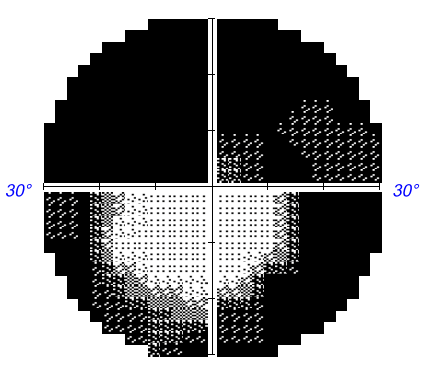

Fluorescein angiography appeared to show a delayed choroidal filling (bit unfortunate that the watershed zone is at the border of the image)

Unfortunate that the watershed area is right at the border of the photo, but the delayed filling can be recognised

Given:  a) the patient's age; b) the ESR level; c) the CRP level; d) photographic and angiographic documentation of a sectoral choroidal filling defect from 3:00 to 4:00; e) pallid optic disc swelling; and f) preservation of vascular clarity over the surface of the swollen disc, a diagnosis of arteritic AION appears to be likely.